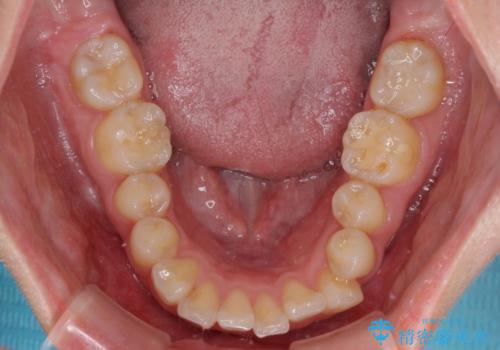

- 上顎前歯の突出感と、前歯のクロスバイトを気にして来院された患者様です。

前歯の叢生と口元の閉じにくさを気にして来院された患者様です。

奥歯の咬み合わせを見ると、上顎が下顎に対して相対的に前方にありました。

口元の閉じにくさを改善するためには、上顎臼歯を後方に移動させた咬み合わせにする必要があります。

インビザライン単体で改善することも可能ですが、達成する可能性が高くないため、カリエールディスタライザーという補助装置を併用して、より確実性を上げることとしました。

奥歯の咬み合わせを改善しながら、並行してインビザラインで歯列を整えることとしました。